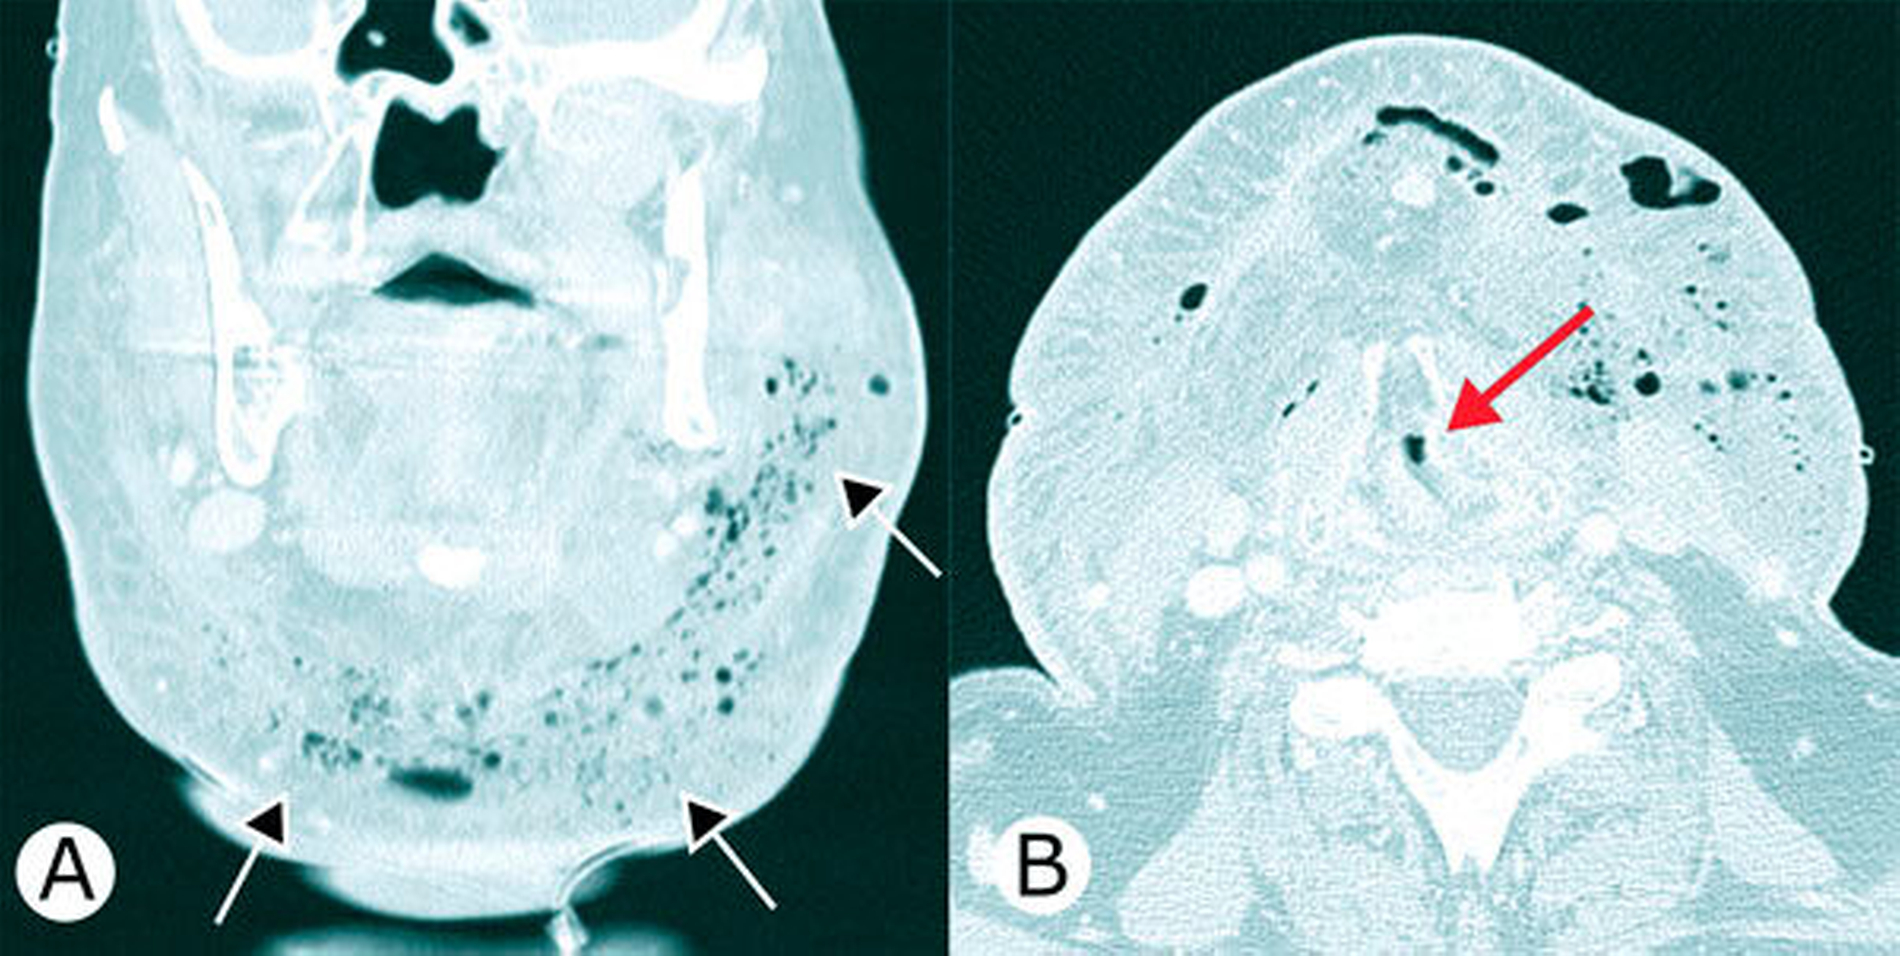

Die Computertomografie zeigte in den Halsweichgeweben beidseits eine ausgedehnte Abszedierung mit Gasbildung und Einengung des Atemwegs (Abbildung 2).